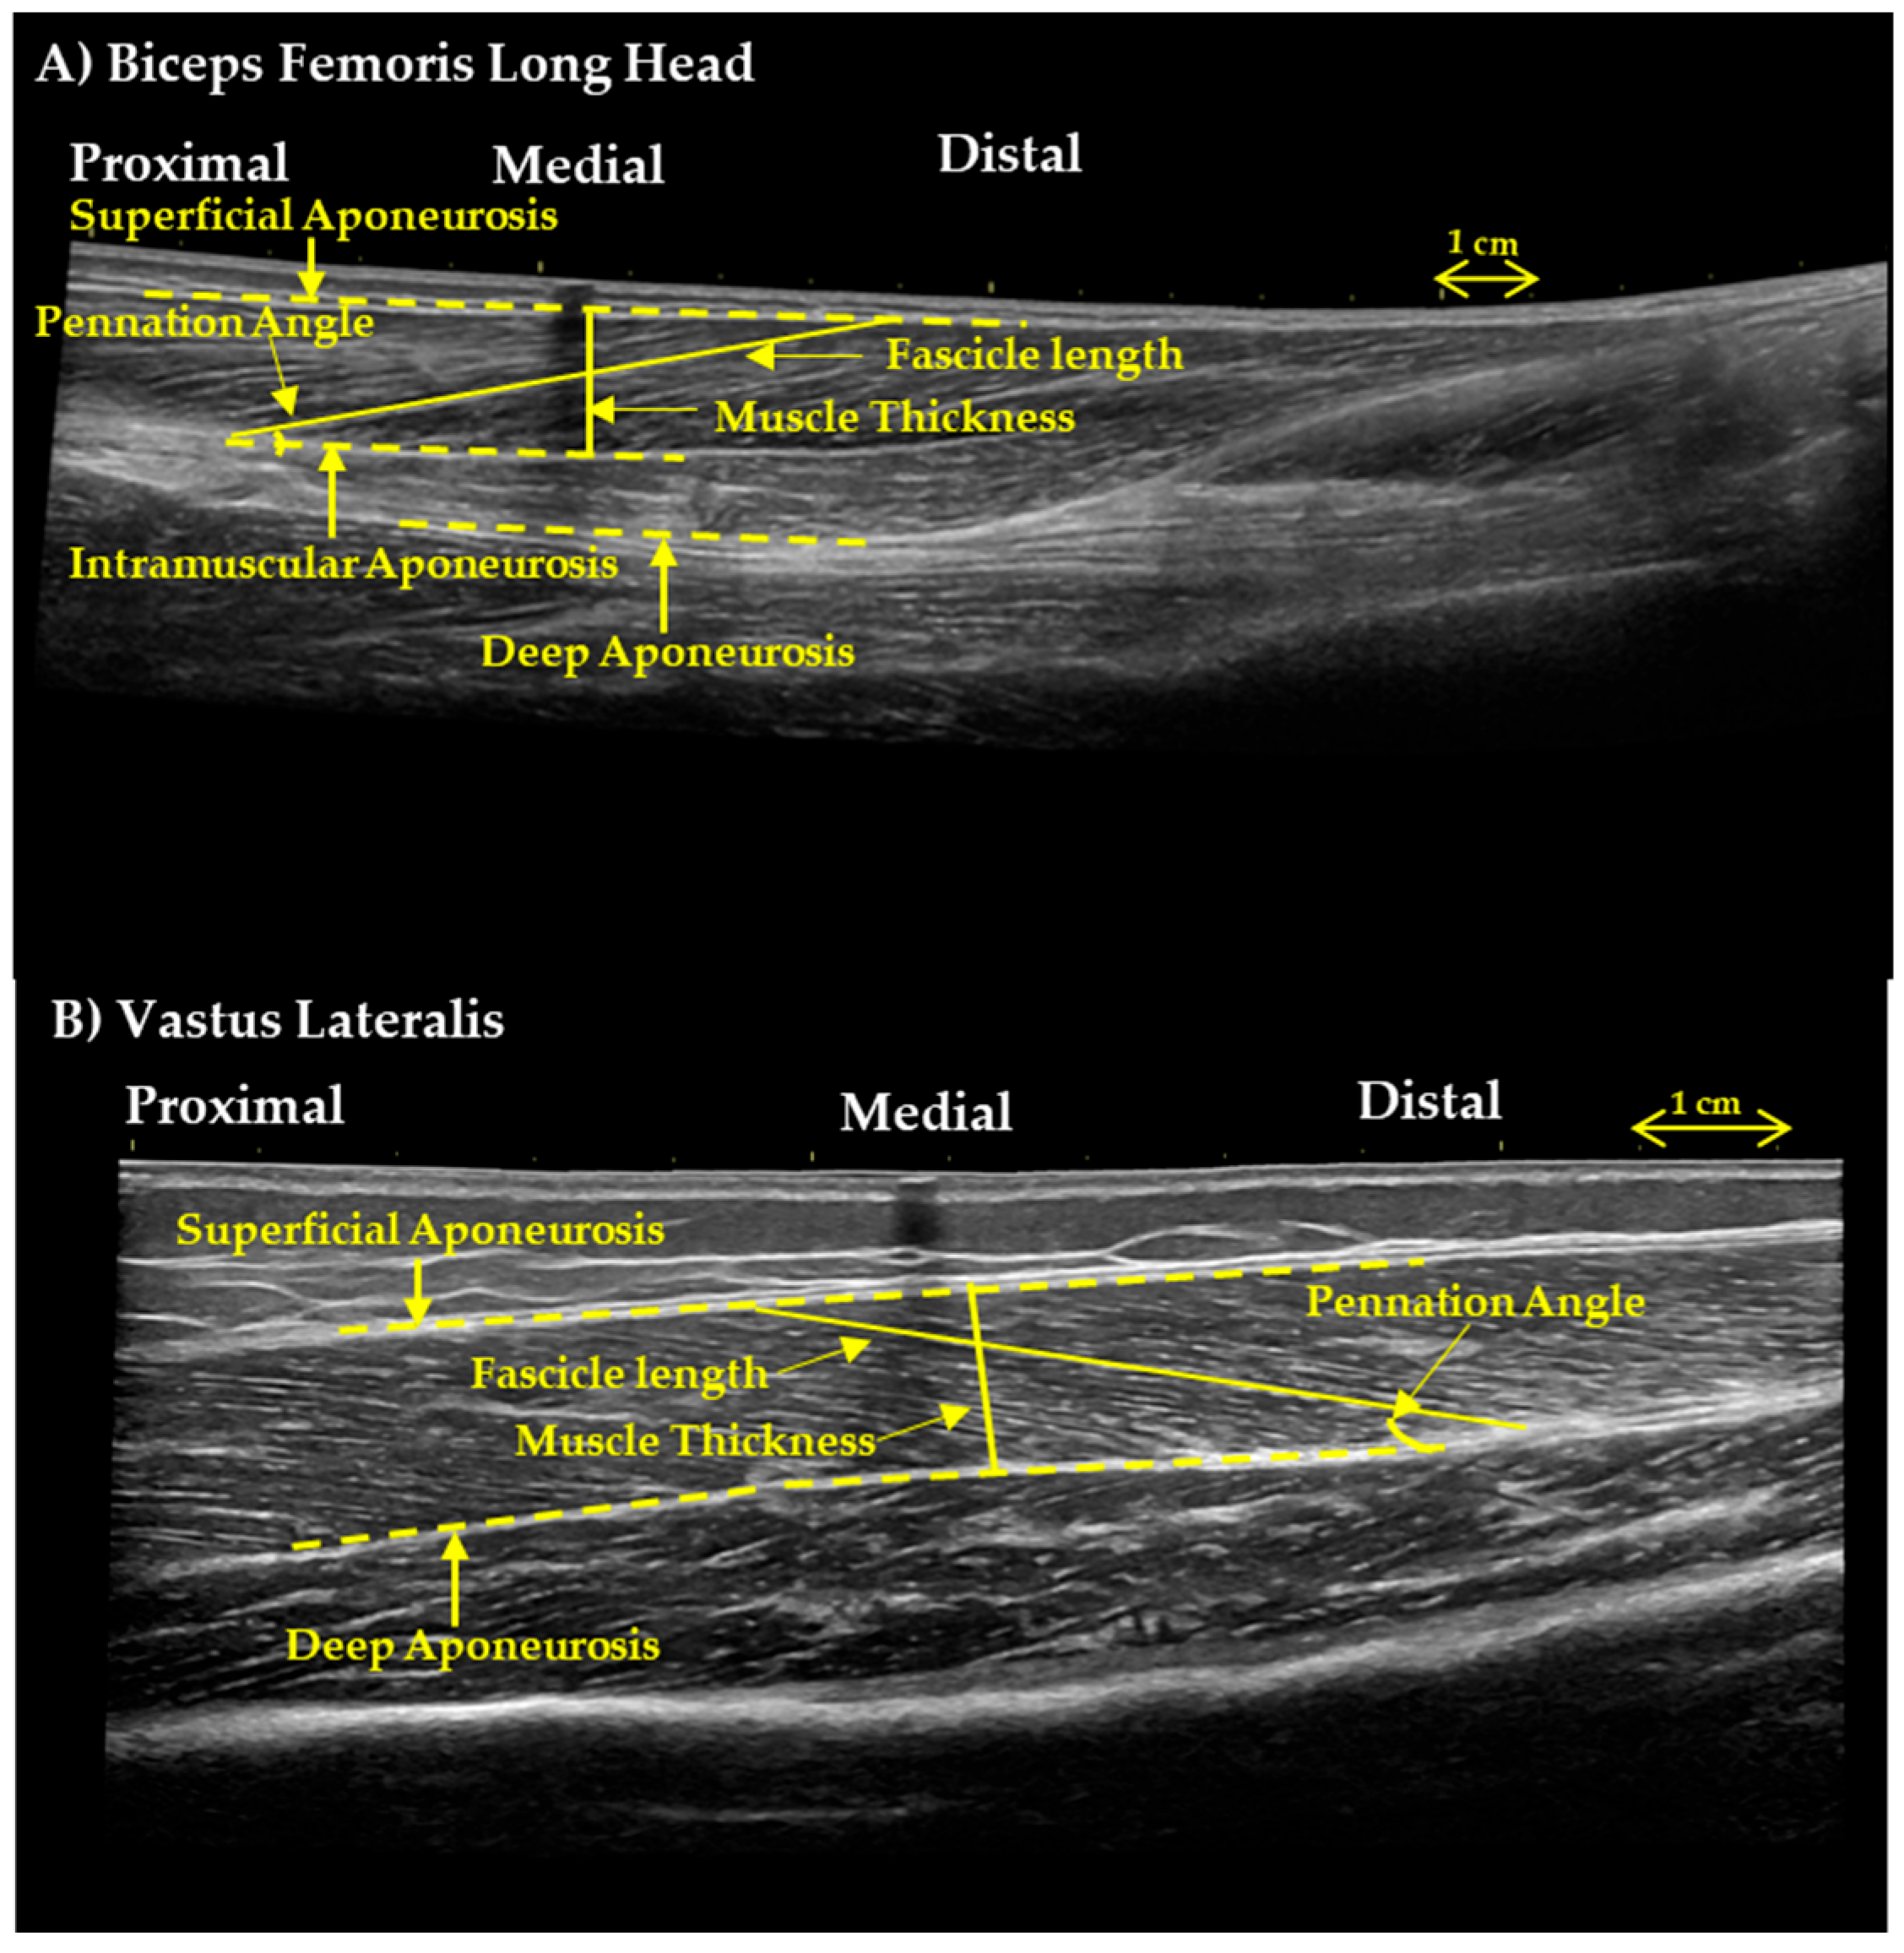

Ultrasound images were obtained in the morning, 24 h after the last training session. Participants rested in a supine position on a physiotherapy bed for 20 min with muscles relaxed, hips at 180°, and knees extended (~170°). VL architecture was measured at the midpoint of the muscle, 50% of the distance from the greater trochanter to the lateral femoral condyle [31]. GM and GL were measured at one-third (30%) of the distance from the popliteal crease to the center of the medial malleolus, and BF was measured at the midpoint (50%) from the ischial tuberosity to the fibular head. All measurements were performed on the right leg. Panoramic B-mode ultrasound images were acquired using a LOGIQ S9 system (General Electric, Boston, MA, USA) with an ML6-15 MHz linear array probe in extended field-of-view mode. Acoustic contact was maintained with Aquasonic clear gel (Parker Laboratories, New Fairfield, NJ, USA). The transducer was positioned longitudinally along the femur, parallel to the muscle fascicles, and perpendicular to the skin. A scanning path was marked on the skin with dashed lines (~10 cm) on either side of the 50% muscle length marker [32]. Images were analyzed using Motic Images Plus software (2.0, Motic, Hong Kong, China). For each participant, two FLs and their respective PAs were measured. MT was defined as the perpendicular distance between the superficial and deep aponeuroses and measured twice [33] (Figure 2). Anatomical cross-sectional area (CSA) was also assessed for VL, GM, GL, and BF, with average values used for analysis (Figure 3). FL of the lower limb muscles was scaled to respective bone length (e.g., tibia or femur length) to account for inter individual differences in skeletal dimensions and enable comparisons of muscle architecture across subjects (Table 1). Test–retest reliability was determined in 11 participants on two separate days. Intraclass correlation coefficient (ICC) for MT was 0.970 (90% CI: 0.913–0.990), for PA ICC was 0.942 (90% CI: 0.836–0.980), and for FL ICC was 0.948 (90% CI: 0.854–0.982).

Figure 2. Panoramic ultrasound images of (A) biceps femoris long head and (B) vastus lateralis.